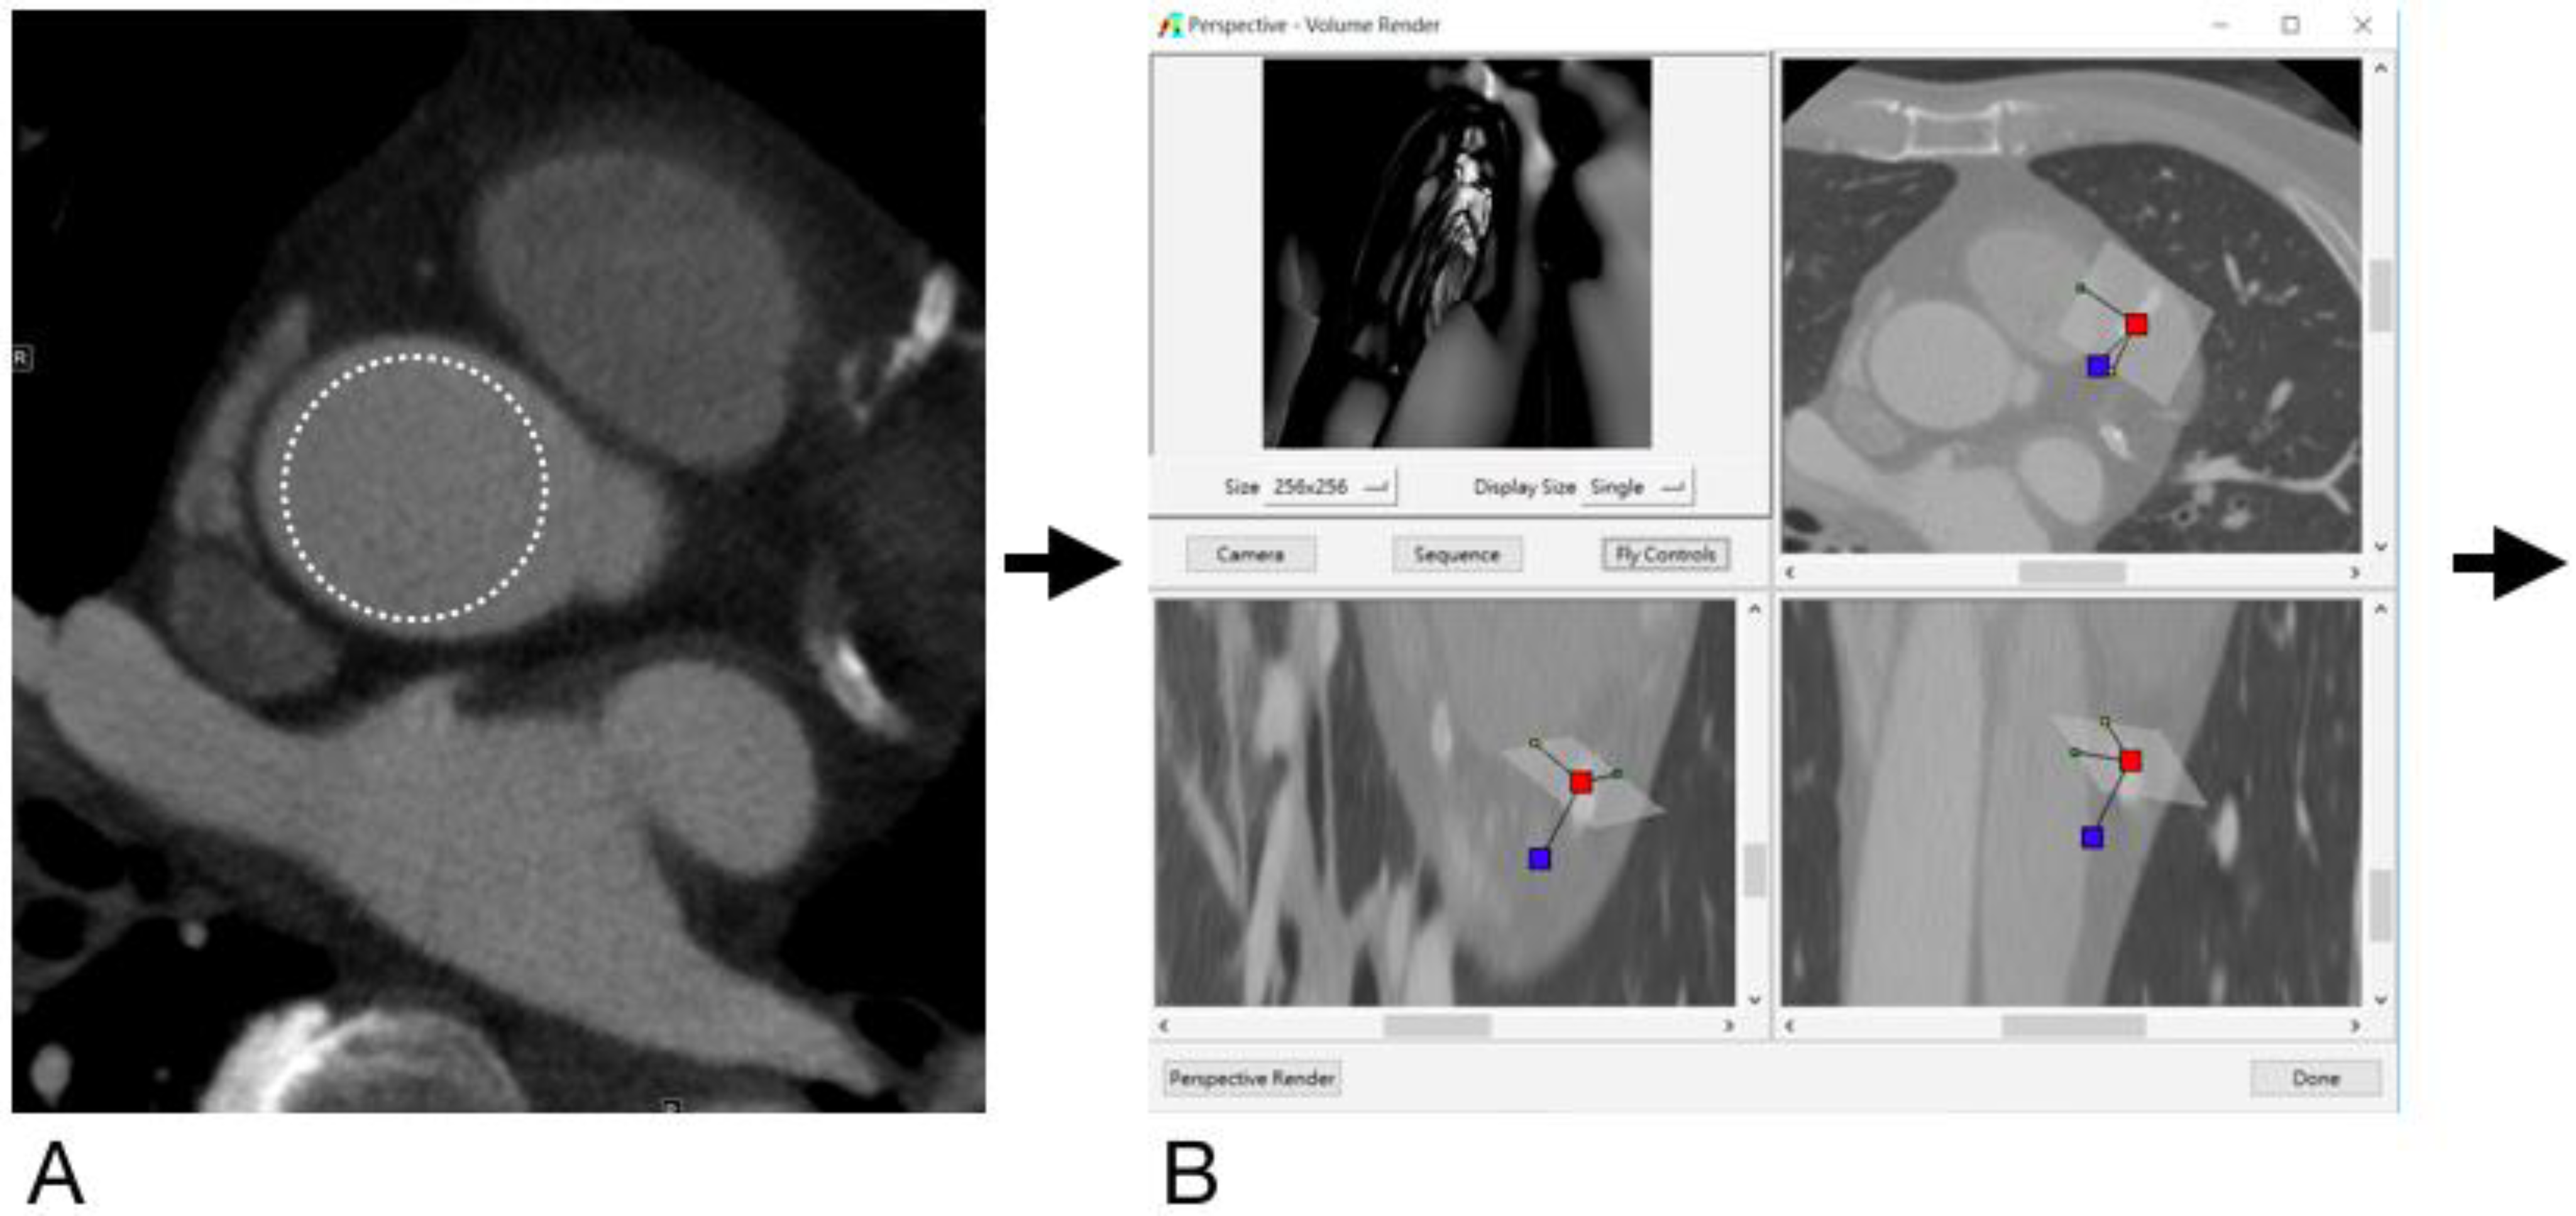

From www.mdpi.com

Diagnostics Free FullText Added Value of Computed Tomography Endoscopy For Heart Blockage A doctor places a long, thin flexible tube called a catheter in a blood vessel, usually in the groin or wrist. This heart blockage treatment without surgery can take anywhere from thirty minutes to several hours. During an endoscopy, a healthcare provider places a long, thin tube (endoscope) inside your body. It's guided to the heart. An endoscopy is a. Endoscopy For Heart Blockage.